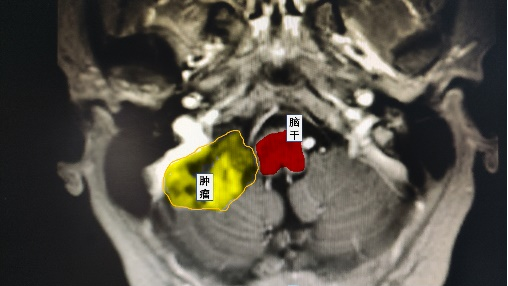

近日,鄰玉鎮(zhèn)楊女士在做體檢時(shí)意外發(fā)現(xiàn)“小腦占位”,緊貼腦干的兇險(xiǎn)位置,讓她感到驚恐和困惑。幸運(yùn)的是,她了解到瀘州市中醫(yī)醫(yī)院神經(jīng)外科與華西醫(yī)院合作,具有一流的醫(yī)療水平,便前往尋求專業(yè)的診治。

根據(jù)術(shù)前的規(guī)劃,謝勇主任通過使用神經(jīng)外科顯微鏡成功暴露出了小腦腫瘤組織,并與華西教授共同切除了緊貼著腦干和包繞顱底顱神經(jīng)的腫瘤組織。術(shù)后患者無神經(jīng)功能障礙,順利出院。